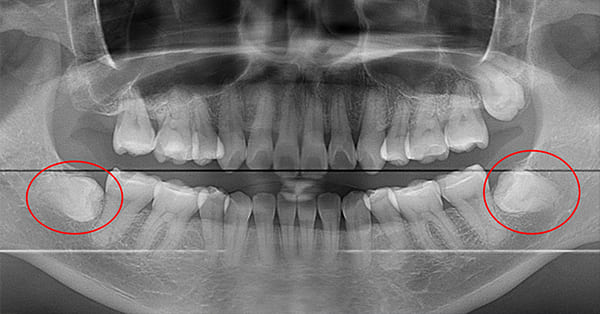

パノラマレントゲン

-

親知らずの種類

斜めに生えている親知らず

親知らずが斜めに生えていて、隣の歯にぶつかって圧迫してしまうタイプです。

このタイプが最も多く、虫歯になりやすいだけでなく、隣の歯を圧迫し、咬み合わせや歯並びに影響が出る場合もあるので、抜歯をおすすめします。